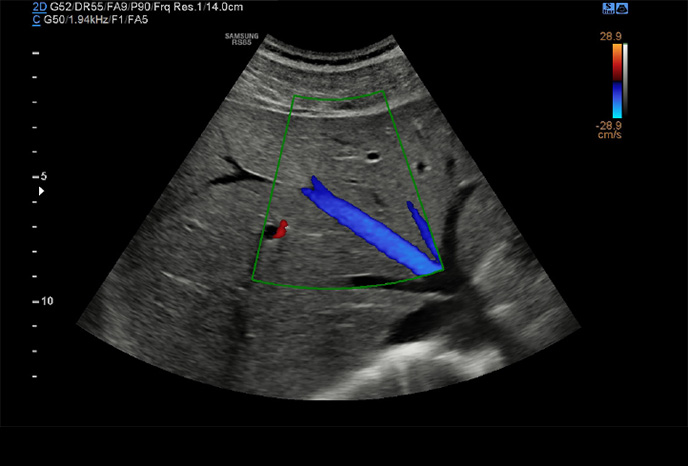

Trojrozměrná vizualizace průtoku krve

LumiFlow ™ je funkce, která vizualizuje průtok krve trojrozměrně, tak aby usnadnila intuitivně pochopit strukturu průtoku krve a malých cév.